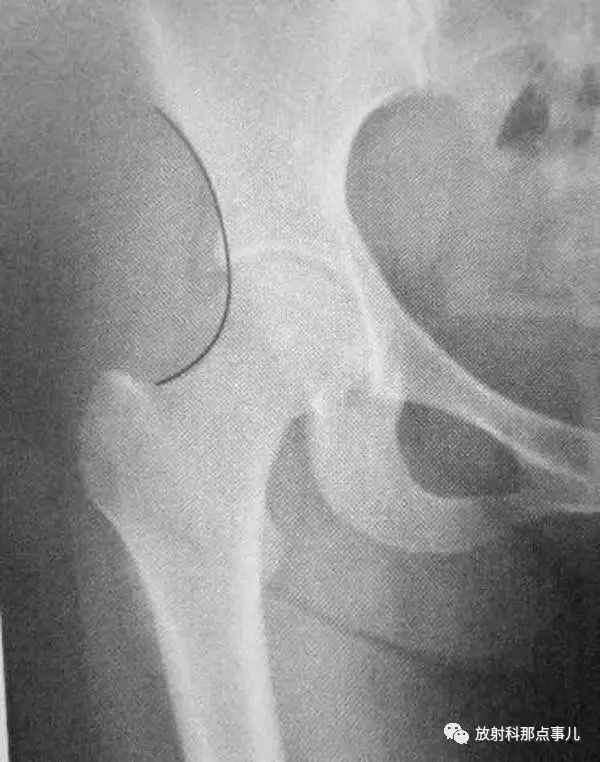

Kline线

沿股骨颈上缘划线并沿股骨头方向的延长线。正常此线应该切割部分股骨头骨骺,若骨骺位于该线内侧,提示股骨头骨骺向下滑脱。